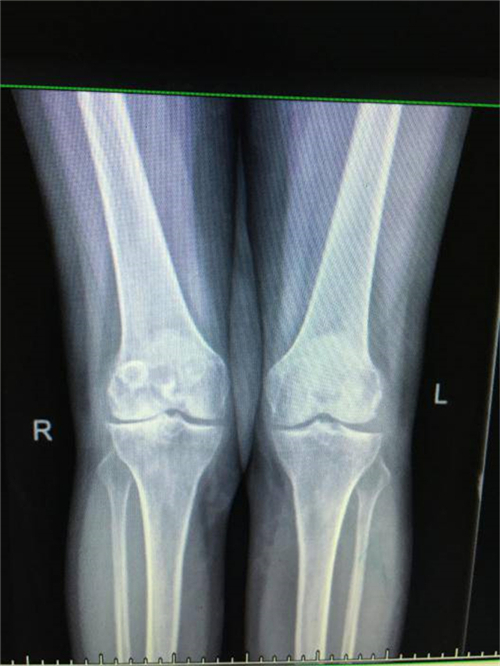

得知郴州市第四人民医院骨科掌握了这一手术技术,便前来就诊。谭主任接诊到该患者后,对其进行了详细的体格检查,发现其左膝关节僵直,屈伸活动不能,负重时膝关节疼痛明显加重,膝关节X线片提示膝关节退变严重,关节间隙明显变窄,并有游离体形成,诊断为左膝关节重度骨关节炎并关节僵直,有明确的膝关节置换手术指征。

术前X线